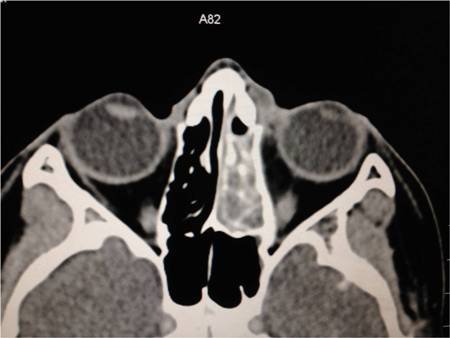

Peri-orbital cellulitis: inflammation of peri-orbital tissues anterior to the orbital septum; absence of orbital inflammation.[Figure caption and citation for the preceding image starts]: Axial CT post contrast: opacified ethmoid and frontoethmoidal recess on the left sideFrom the personal collections of H. Jane Kim, MD, and Robert Kersten, MD, UCSF; used with permission [Citation ends].

Orbital cellulitis: inflammation of orbital tissues located deep to the septum.

inflammation of peri-orbital or orbital tissue; sub-periosteal abscess (commonly superomedial or inferomedial); sinusitis